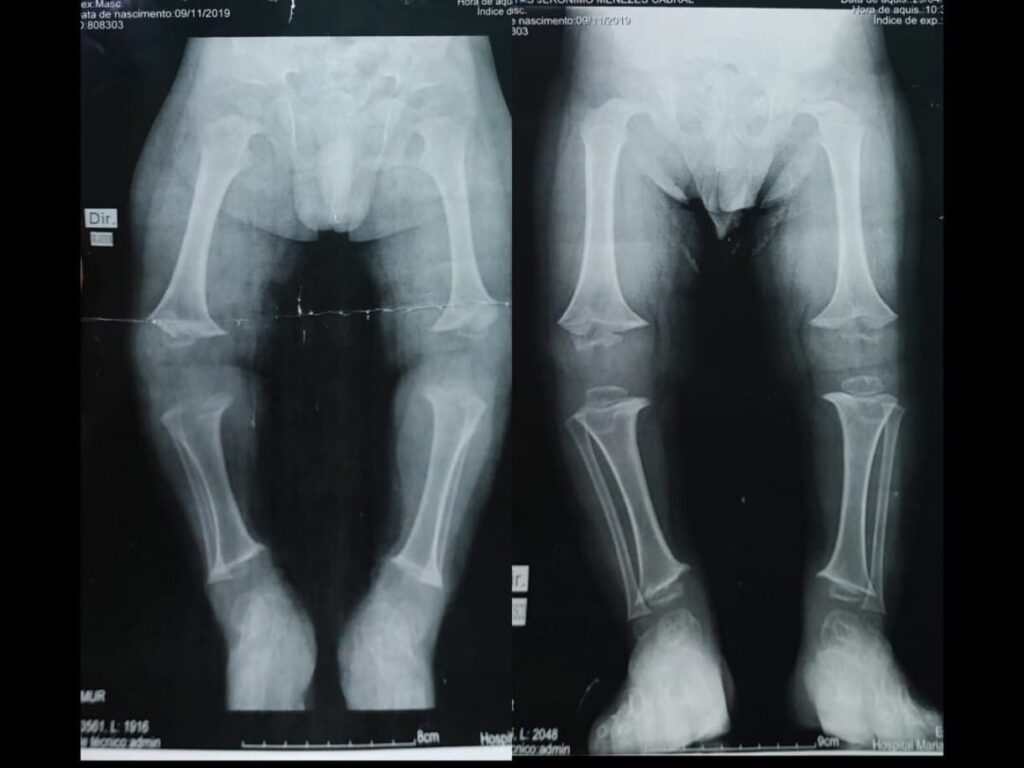

“Alice teve diminuição de crises de sinusite e otite que antes eram muito frequentes e hoje não reclama de dor nenhuma. Todas as mães de crianças com acondroplasia com as quais já conversei falam sobre as dores. Percebemos mudanças nas proporções do corpo e muitas mudanças na autonomia. Hoje ela faz muitas coisas sozinha que antes não conseguia como ir ao banheiro e subir escadas. O arqueamento das pernas – característica comum da condição – também diminuiu muito. Eu não consigo imaginar Alice parando com essa medicação, voltando a sentir dores, a ter desproporções e pernas mais arqueadas. Esse remédio pra mim é importante como a vida”, completa.

Decorrente de mutações no gene FGFR3, a acondroplasia é a causa mais comum de displasia óssea que leva à baixa estatura desproporcional. Como implica em alterações no desenvolvimento da cartilagem das placas de crescimento, o quadro resulta em baixa estatura. Em média, os homens têm 1,31 m de altura, enquanto as mulheres possuem 1,24 m. Além disso, é comum o encurtamento de pernas e braços, cabeça e testa são proeminentes e há uma desproporção corporal de limitações físicas visíveis já no nascimento.

Minha neta Alice Gonçalves Barcelos,teve melhora mais que considerável com o uso da medicação ,o arqueamento das pernas é o mais visível e hoje o crescimento mensal dela acompanha de acordo em centímetros por mês….